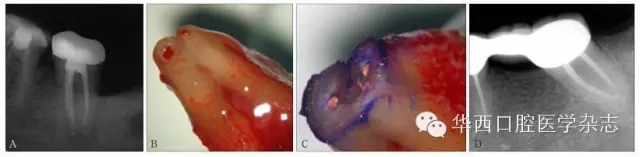

A:42牙術前X線根尖片示根充至距影像學根尖0.5~1 mm內(nèi);B:顯微外科根尖手術術中切除根尖,體視顯微鏡 × 40。藍色箭頭示根尖段根管內(nèi)殘留壞死牙髓組織及感染物質(zhì),黑色虛線示根尖段根管,紅色箭頭示原牙膠充填止點。

圖4 X線根尖片未準確指示根管工作長度

A:37牙術前X線根尖片示根充至距影像學根尖0.5~1 mm;B:37牙行意向性牙再植術,拔出后可見根尖牙膠超填,解剖學根尖孔距解剖學根尖有一定距離;C:截取根尖3 mm,甲苯胺藍染色示C型根管;D:47牙根管治療10年回訪,X線根尖片顯示,雖充填物距離影像學根尖約3 mm,但愈后良好。

圖5 X線根尖片評估復雜根管系統(tǒng)根管工作長度存在局限性